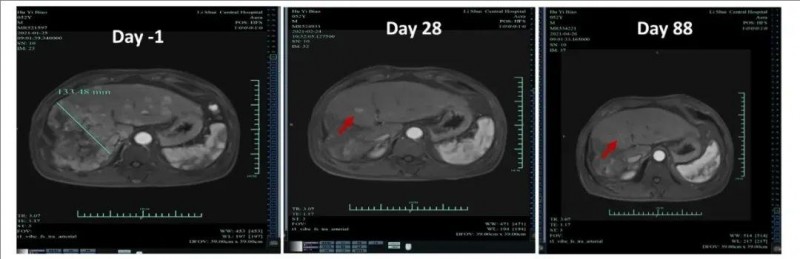

值得一提的是,其中1例达到部分缓解(PR)的患者(012号患者),在Ori-CAR-001 CAR-T细胞治疗后第28天,肿瘤减小率超过93%,靶肿瘤病灶从治疗前最大肿瘤直径133mm,显著缩小至9mm。并在治疗第88天,复查MRI发现,肿瘤几乎完全消失(详见下图)。

▲图源“ASCO”,版权归原作者所有,如无意中侵犯了知识产权,请联系我们删除